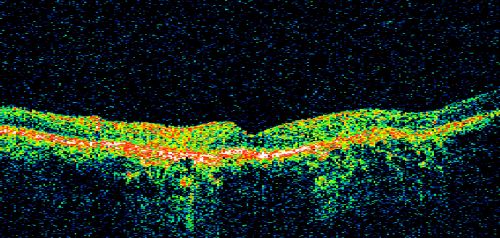

Geographic Atrophy and Age-Related Macular Degeneration - Choriocapillaris is Largely Still Intact

85-year-old woman has age-related macular degeneration in both eyes with geographic atrophy.  She has noticed her vision getting slightly worse in the past 6 months. VISUAL ACUITY:  OD 20/70, OS 20/400